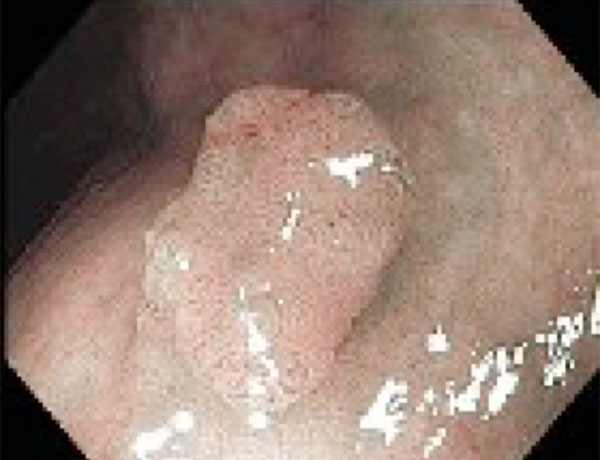

Barrett Hastalığı

Barrett Hastalığı Nedir? Ne Kadar Ciddi Bir Sorundur?

Barrett özofagus, yemek borusunun alt ucundaki normal skuamöz epitelyumun, uzun süreli reflü nedeniyle bağırsak tipi kolumnar epitele dönüşmesi durumudur. Bu durum, metaplazi olarak tanımlanır ve bazı hastalarda displazi ya da yemek borusu adenokarsinomu riskini artırabilir.

Barrett Hastalığı ve Yemek Borusu Kanseri Riski

Barrett hastalığı, yemek borusu alt ucundaki dokunun, mide içeriği ile uzun süreli temasa maruz kalması sonucu değişime uğramasıdır. Bu değişim zamanla displazi gelişmesine ve daha ileri düzeyde adenokarsinom (yemek borusu kanseri) oluşmasına neden olabilir. Barrett hastalığının adenokarsinom gelişme riski, displazinin düzeyine göre değişir:

- Non-displastik Barrett: %0.1–0.3/yıl

- Düşük dereceli displazi: %0.5–1/yıl

- Yüksek dereceli displazi: %5–10/yıl

Bu nedenle Barrett hastalarının düzenli endoskopik takip altında olması büyük önem taşır.